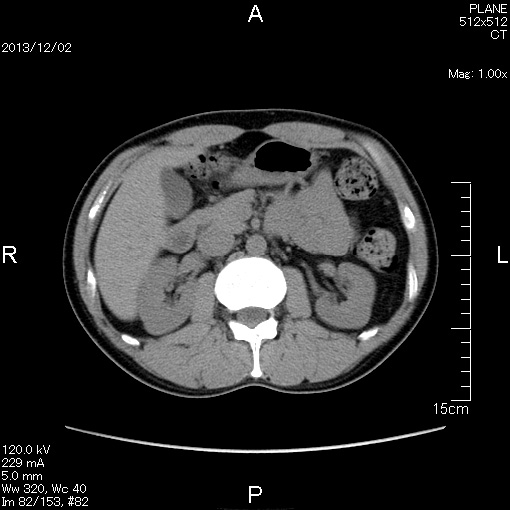

2006年入院治療の退院日から10年。 かなり大きな節目なんだが、なんだろうこの軽い感じは(笑)。 「10年生きたんだぁ」くらい。 変わったような変わっていないような。 当時は10年後なんて全く考えていなかった。 今も10年後は考えていないが・・・。 退院前日の2006/10/31は46.6kgだった。 今日計ったら54.8kg。体脂肪は16.6%。 とても健康にストレスなく生活できていることに、治療当時から現在に至るまで、関わった人全員に感謝の気持ちです。 マーカー、CT画像、問題なし!! 血液検査結果もほとんど文句なしの正常値。 そうだなぁ、数値に出ない異変としては、肩凝りかなぁ。 一旦夏になくなったと思ったが、初秋から再発。 マウスを左手にしたり、シップ貼ったり、最近はホッカイロ貼ったり。 で、一向に良くなる気配がない。 やはり四十肩なのか。 でも肩の可動域は問題ない。動かせないような痛みも無い。 結局色々考えてたどり着いたのは「変形性頚椎症」ではないかと。 肩凝りや頭痛がダラダラと続くようになるという症状がピッタリ当てはまる。 さて、改善策がなかなか難しい。 整形外科行ってもレントゲン撮って湿布をくれるだけだろう。 そんなことに大金を出すならまずは300円/回のプールで泳ごうと思う。 重力から開放して全身運動をするのが一番良いらしい。 2015年の目標は少しでも良いから水泳を再開する、だな。 マーカー、CT画像、問題なし!! 通常の血液検査結果も文句なしの正常値がズラ~っと並んだ!! 間違いなくヨメの食事のおかげである。ほんとうに感謝である!! ちなみに最近少々腰周りの肉付きが気になっていたのだが・・・。 左から2013年12月、2013年06月、2012年12月と背骨の位置は合わせて並べてみた。 6月まではあまり変化がなかったが、この半年で明らかに違う。 背中側の脂肪がやや増えてはいる。 でも最も大きな違いは、腸なのか、やたらと内臓が膨れている・・・。 一言で言うと食べすぎ?!?! 食事は野菜中心ではあるが、確かによく食べているw。 せっかくスーツのウエストを詰めたんだからこれ以上にならないようにしたい。 「腹八分目を心がける」かな。